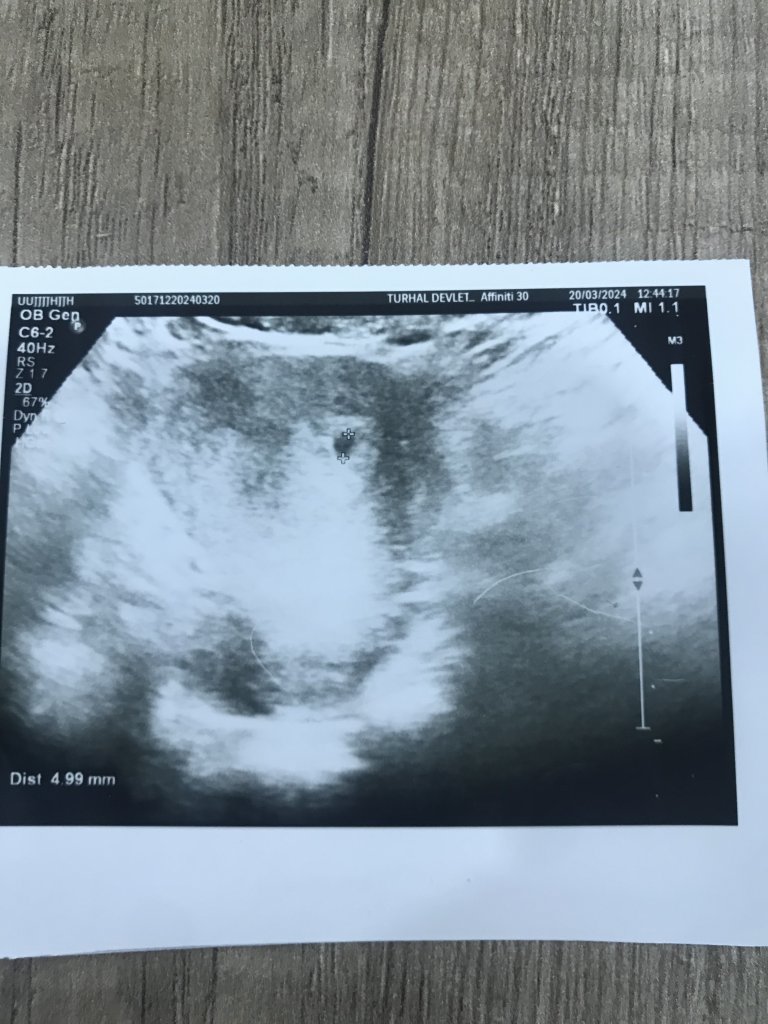

İkiz gebelik olabilir mi kızlar kesenin üstündeki ikinci kese olabilir mi sizce ? Beta değerim ilk öğrendiğimde 8

5 mart 8

7 mart 33

9 mart 104

12mart 285

16 mart 1428

20 mart 4128

Doktor 4 haftalık dedi